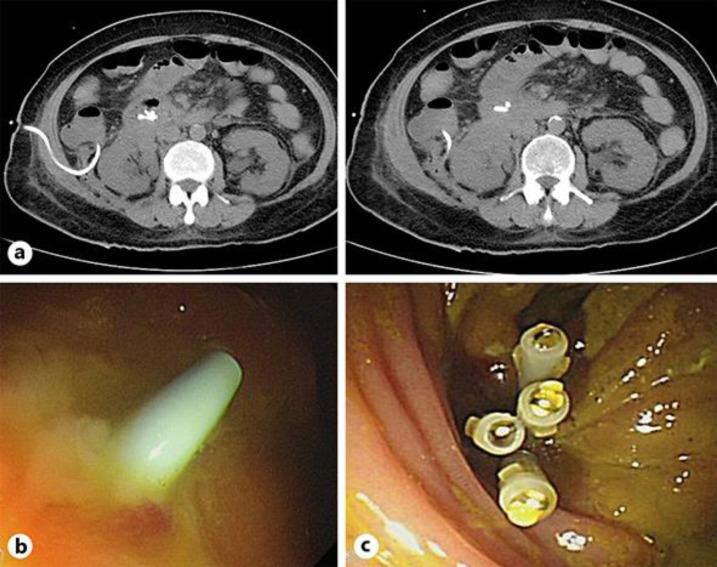

Endoscopic retrograde cholangiopancreatography (ERCP) is a high-risk procedure with a significantly high rate of complications, such as pancreatitis, bleeding, perforation, and infection. Pancreatitis is the most common post-ERCP complication with an incidence of approximately 3.5%. Although perforation is a rare complication with an incidence of 0.1-0.6%, it may be associated with a high rate of mortality of 1.0-1.5%. Here, we report a rare case of ERCP-induced double iatrogenic perforations in the duodenum and colon complicated by an intra-abdominal abscess. The post-ERCP perforation was successfully sealed using fibrin glue (Tisseel). The intra-abdominal abscess was treated with a computed tomography-guided pigtail drainage; however, the pigtail spontaneously migrated and perforated the ascending colon. The pigtail was removed, and closure of the colon perforation was successfully achieved with endoscopic clipping. Tisseel spray can be a treatment option for post-ERCP perforations. Careful consideration of procedural complications, early detection of perforations, and prompt treatment can be life-saving.

内镜逆行胰胆管造影术(ERCP)是一种高风险操作,并发症发生率显著较高,如胰腺炎、出血、穿孔和感染。胰腺炎是ERCP术后最常见的并发症,发生率约为3.5%。虽然穿孔是一种罕见并发症,发生率为0.1 - 0.6%,但可能伴有1.0 - 1.5%的高死亡率。在此,我们报告一例罕见的ERCP导致十二指肠和结肠双医源性穿孔并伴有腹腔脓肿的病例。ERCP术后穿孔通过纤维蛋白胶(Tisseel)成功封闭。腹腔脓肿采用计算机断层扫描引导下猪尾引流治疗;然而,猪尾自行移位并导致升结肠穿孔。移除猪尾后,通过内镜夹闭成功实现结肠穿孔的闭合。Tisseel喷雾可作为ERCP术后穿孔的一种治疗选择。仔细考虑操作并发症、早期发现穿孔并及时治疗可挽救生命。